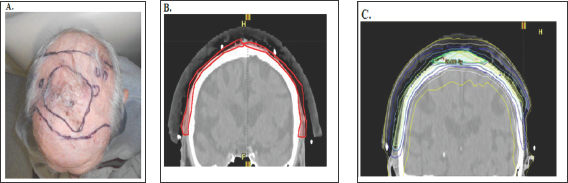

Figure 9: Photographs and CT plans of a patient preparing for VMAT.

A: Mark up of a scalp field at planning showing areas of gross tumour within the area of ESFC.

B: CTV is contoured on the planning scan. Red volume represents ESFC.

C: The resultant dosimetry avoiding brain. The dose homogeneity is uniform throughout the target. The dose profile across the field is uniform with no need for junctioning radiation fields. Green volume represents gross tumour.

C)The use of Intensity modulated radiotherapy (IMRT). IMRT, using automated multileaf collimators in the head of the linac, enables the intensity of the beam to be modified during beam-on time, sculpting the dose to the contoured volumes. Prior to this advance radiotherapy was initially Two Dimensional (2D) and based on fields. The application of CT technology in planning accelerated the uptake of progression to Three Dimensional Conformal Radiotherapy (3DCRT) with the concept of volume treatment. However, RT still came in "blocks" IMRT allowedtreatment around curves, especially sparing dose to OARs in the concavity of a volume requiring treatment (e.g. brain underneath a scalp)

The significance of these advantages for skin cancer is that radiotherapy can now treat large curved convex surfaces, such as those found in ESFC. Large convex surfaces of ESFC can be found covering anatomical sites such as the scalp, forehead, cheeks, forearms, legs, chest, upper back, and shoulders, VMAT can now be used to treat these skin surfaces with definitive MVT photon RT (Figure 9). These advances have overcome the problems of traditional RT. The dose can now be more uniform throughout the target, with no need for junctioning radiation fields.